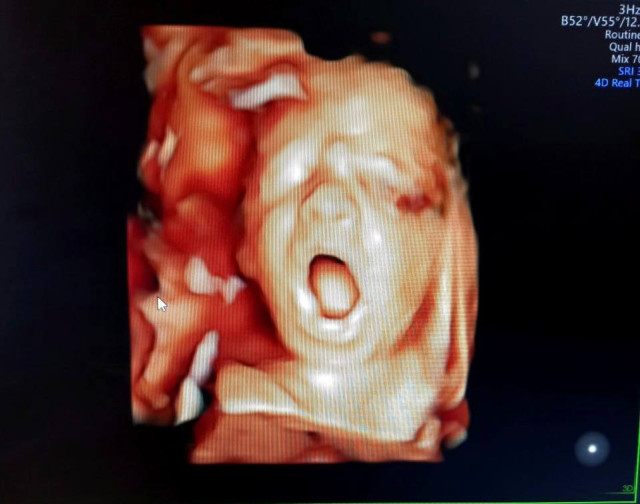

Завідувач відділення ультразвукової діагностики Сергій Грибчук пояснює: «Ці функції ми можемо використовувати вже при першому скринінгу, щоб побачити малюка детальніше. Риси тата і мами завдяки режиму 3-D найкраще можна роздивитися з 26 до 30 тижня вагітності: носик, вушка, губи, очі, навіть їхню міміку. Буває, що пари сперечаються про те, чиї у маляти ніс чи вушка. Також дуже добре бачимо рухи малюка і можемо подивитись, чим дитина займається в цей момент в животику мами, наприклад, смокче кулачок чи позіхає».